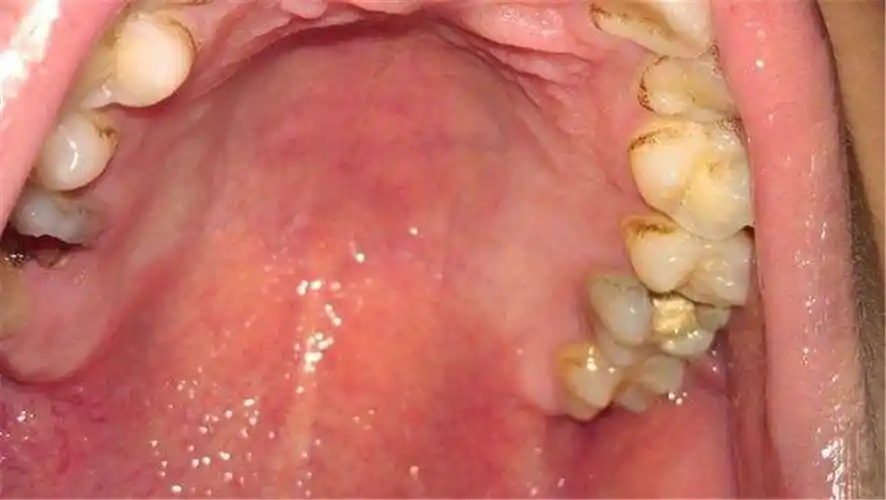

口腔白色念珠菌感染症状图片

口腔念珠菌病

口腔念珠菌病,你了解多少?